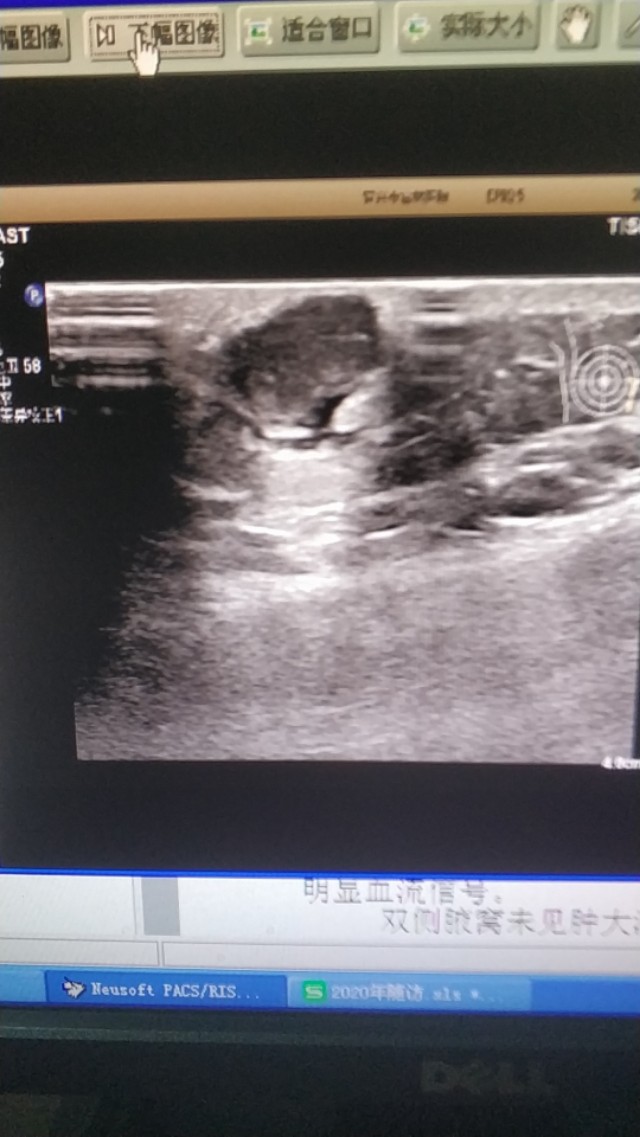

上图是一个左膝部的表皮囊肿,与皮肤真皮层关系密切,里面回声细密伴裂隙样低回声。